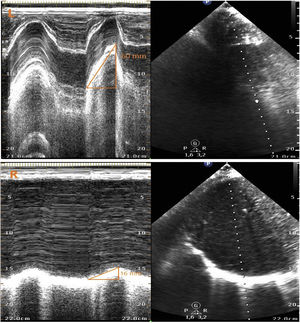

Paciente de 55 años que ingresa en la UCI tras cirugía cardiaca de reparación de comunicación interauricular tipo ostium secundum y drenaje venoso pulmonar anómalo. Tras la extubación, sin incidencias, permanece con hipoxemia sin alteraciones en la radiografía de tórax. Se realiza ecografía pulmonar en la que se objetiva una disminución del movimiento diafragmático derecho en comparación con el izquierdo (vídeo 1). Se mide la excursión diafragmática apreciándose una excursión derecha reducida de 16mm frente a una excursión izquierda de 60mm (fig. 1). Estos hallazgos son compatibles con parálisis diafragmática derecha en relación con una probable lesión del nervio frénico ipsilateral durante la cirugía. Mediante manejo conservador con fisioterapia respiratoria incentivada, la paciente evoluciona favorablemente hasta el alta, aunque con persistencia de la disfunción diafragmática por ecografía.